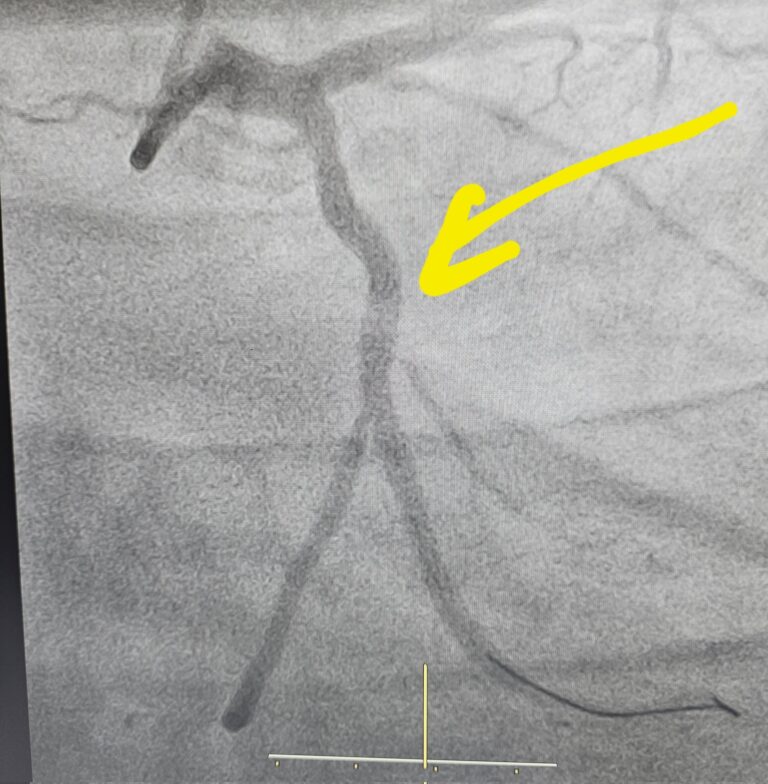

Famous alive cricketers who underwent heart operation and stunt surgery

PC: X Cricket is a good aerobic sport. As a batsman you always have to be on your toes, sneaking those singles and converting those 2 into 3s. But as when a cricketer retires, the work ethic goes down the hill. While most of the heart illnesses are hereditary and genes play a significant role,  lipoprotein(a), some of the cricketers …